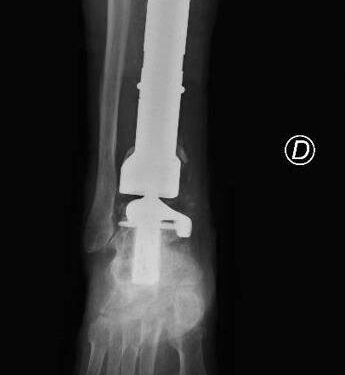

(Adnkronos) – Una protesi di caviglia costruita su misura salva la gamba bionica di Mario, paziente 80enne protagonista di un raro intervento eseguito al Policlinico Gemelli di Roma e definito "unico nel suo genere". Una travagliata storia a lieto fine cominciata una decina di anni fa quando Mario, ex coltivatore diretto, fu colpito da un cancro alle ossa. Ancora oggi, nonostante gli anni e gli acciacchi, Mario continua a occuparsi del suo orticello in una campagna in provincia di Viterbo. Ma sono tanti gli ostacoli che l'anziano ha dovuto superare e che sono iniziati 10 anni fa con un dolore sempre più forte e insistente alla gamba destra. Dopo una serie di esami, l'ortopedico consultato da Mario gli ha comunicato che quei fastidi erano causati da un tumore osseo raro (un adamantinoma) a carico della tibia. Alla diagnosi è seguita la resezione del tumore con impianto di una mega-protesi di tibia prossimale, cioè nell'area vicino al ginocchio. Dopo circa un anno dall'intervento, però, una grave infezione della protesi impiantata ha costretto Mario a subire una serie di complessi interventi chirurgici che si sono conclusi con l'impianto di una protesi totale di gamba e di caviglia in titanio, rivestita in argento per evitare nuove infezioni. Una gamba bionica. Ma ancora non era finita. A distanza di 6 anni, Mario torna dagli ortopedici del Gemelli per un dolore alla caviglia. Gli esami rilevano la rottura di una vite della protesi, a livello della caviglia. E' necessario sostituire il pezzo, ma l'unico modo per farlo – decretano gli specialisti – è facendo confezionare una protesi 'custom-made', disegnata e realizzata su misura. Gli ortopedici del Gemelli inviano perciò la Tac di Mario all'Implantcast, una ditta specializzata di Buxtehude, cittadina a sud ovest di Amburgo, in Germania. Basandosi sulla ricostruzione tridimensionale della caviglia bionica di Mario, i bioingegneri realizzano un calco della protesi custom-made con una stampante 3D, sul quale viene realizzata la protesi in titanio per l'impianto definitivo. Ed ecco l'intervento effettuato da Carlo Perisano, professore aggregato dell'Università Cattolica del Sacro Cuore e dirigente medico presso la Uoc di Ortopedia e Traumatologia della Fondazione Policlinico Gemelli, diretta da Giulio Maccauro. L'operazione dà i suoi frutti: "A distanza di appena qualche giorno dall'intervento, Mario sta di nuovo in piedi sulla sua gamba bionica arricchita di quest'ultimo gioiello tecnologico", riferiscono dall'Irccs capitolino. (segue) —salutewebinfo@adnkronos.com (Web Info)